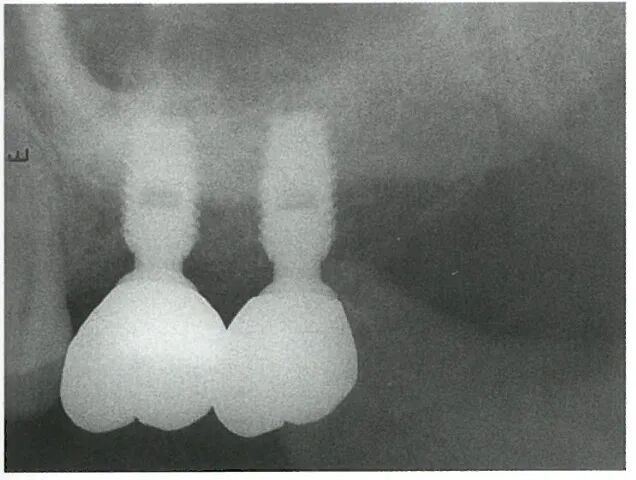

取模后安装最终修复体,牙冠准确到位。

患者戴牙1年后复查,口腔清洁,卫生良好,牙龈颜色、质地正常,26,27 修复体颊侧正中探诊深度约为2mm,患者对治疗效果满意。